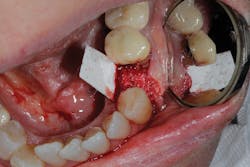

Because of this alveolar resorptive pattern after tooth extraction, bone grafting the extraction socket after tooth extraction procedures has become a solution that attempts to limit the amount of hard- and soft-tissue loss. There are many systematic reviews in the literature that compare the results of residual ridge dimension following tooth extraction after the use of a bone graft (with or without a membrane) versus extraction alone without grafting.7

Indications for bone grafting extraction sites include:

• site development to increase hard and soft tissue for pontic sites in fixed bridge prosthetics (figures 9–14);• correcting bone defects impinging upon anatomical structures after tooth extraction, such as oroantral communication (figure 18); and

• preserving tissue structure for subsequent dental implant therapy.Decision matrix